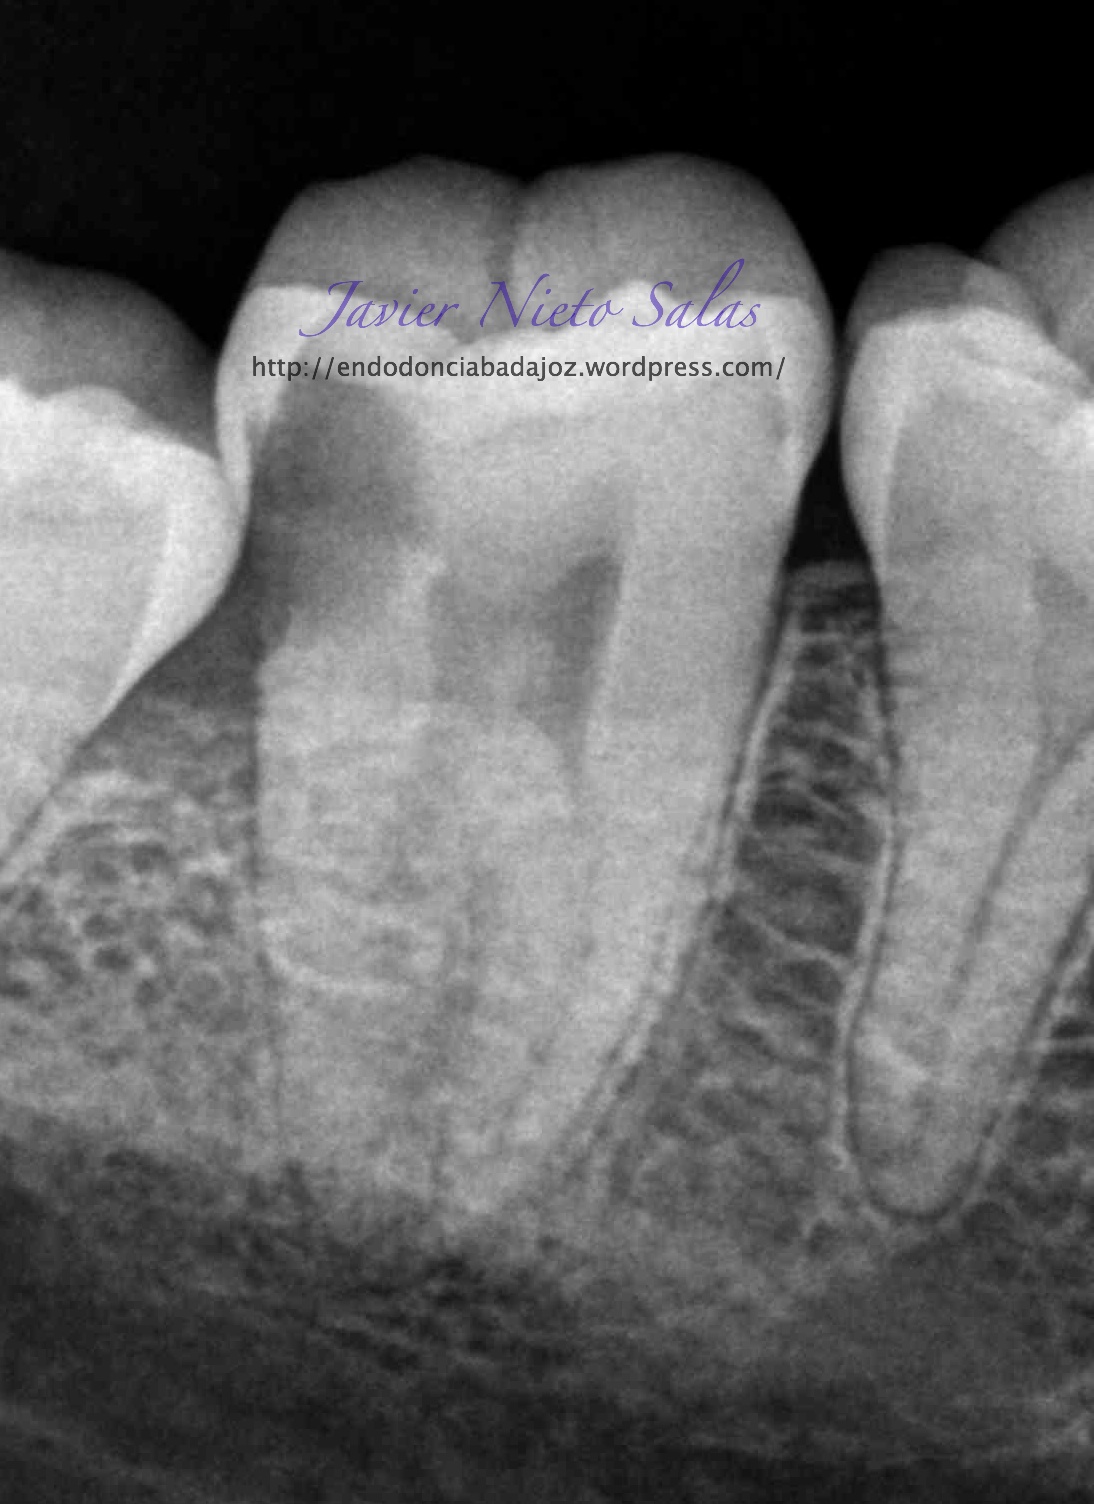

Empezaremos con el primer caso, un 4.7, se trata de una necrosis con afectación periapical.Ante las pruebas diagnósticas, nos fijamos en una fístula muy coronal, un sondaje vestibular puntual, esto nos hace pensar en un diagnóstico diferencial con un Sindrome de Diente fisurado. Sin aparente linea de fisura coronal, no vemos, con la ayuda de la magnificación, linea de fisura, lo que no nos descarta definitivamente que se trate de este síndrome de fisura, pues como ya sabemos pueden aparecer en diferentes tramos de la pieza, clasificando así los diferentes tipos.

Realizamos el tratatamiento de conductos con la sospecha del causante de la necrosis es una fractura vertical, pero no hemos podido ver la linea de fisura.

Se trataría de una cámara pulpar Tipo Ic según la clasificación por el método de Min:

El sistema de Obturación sería con condensación vertical.